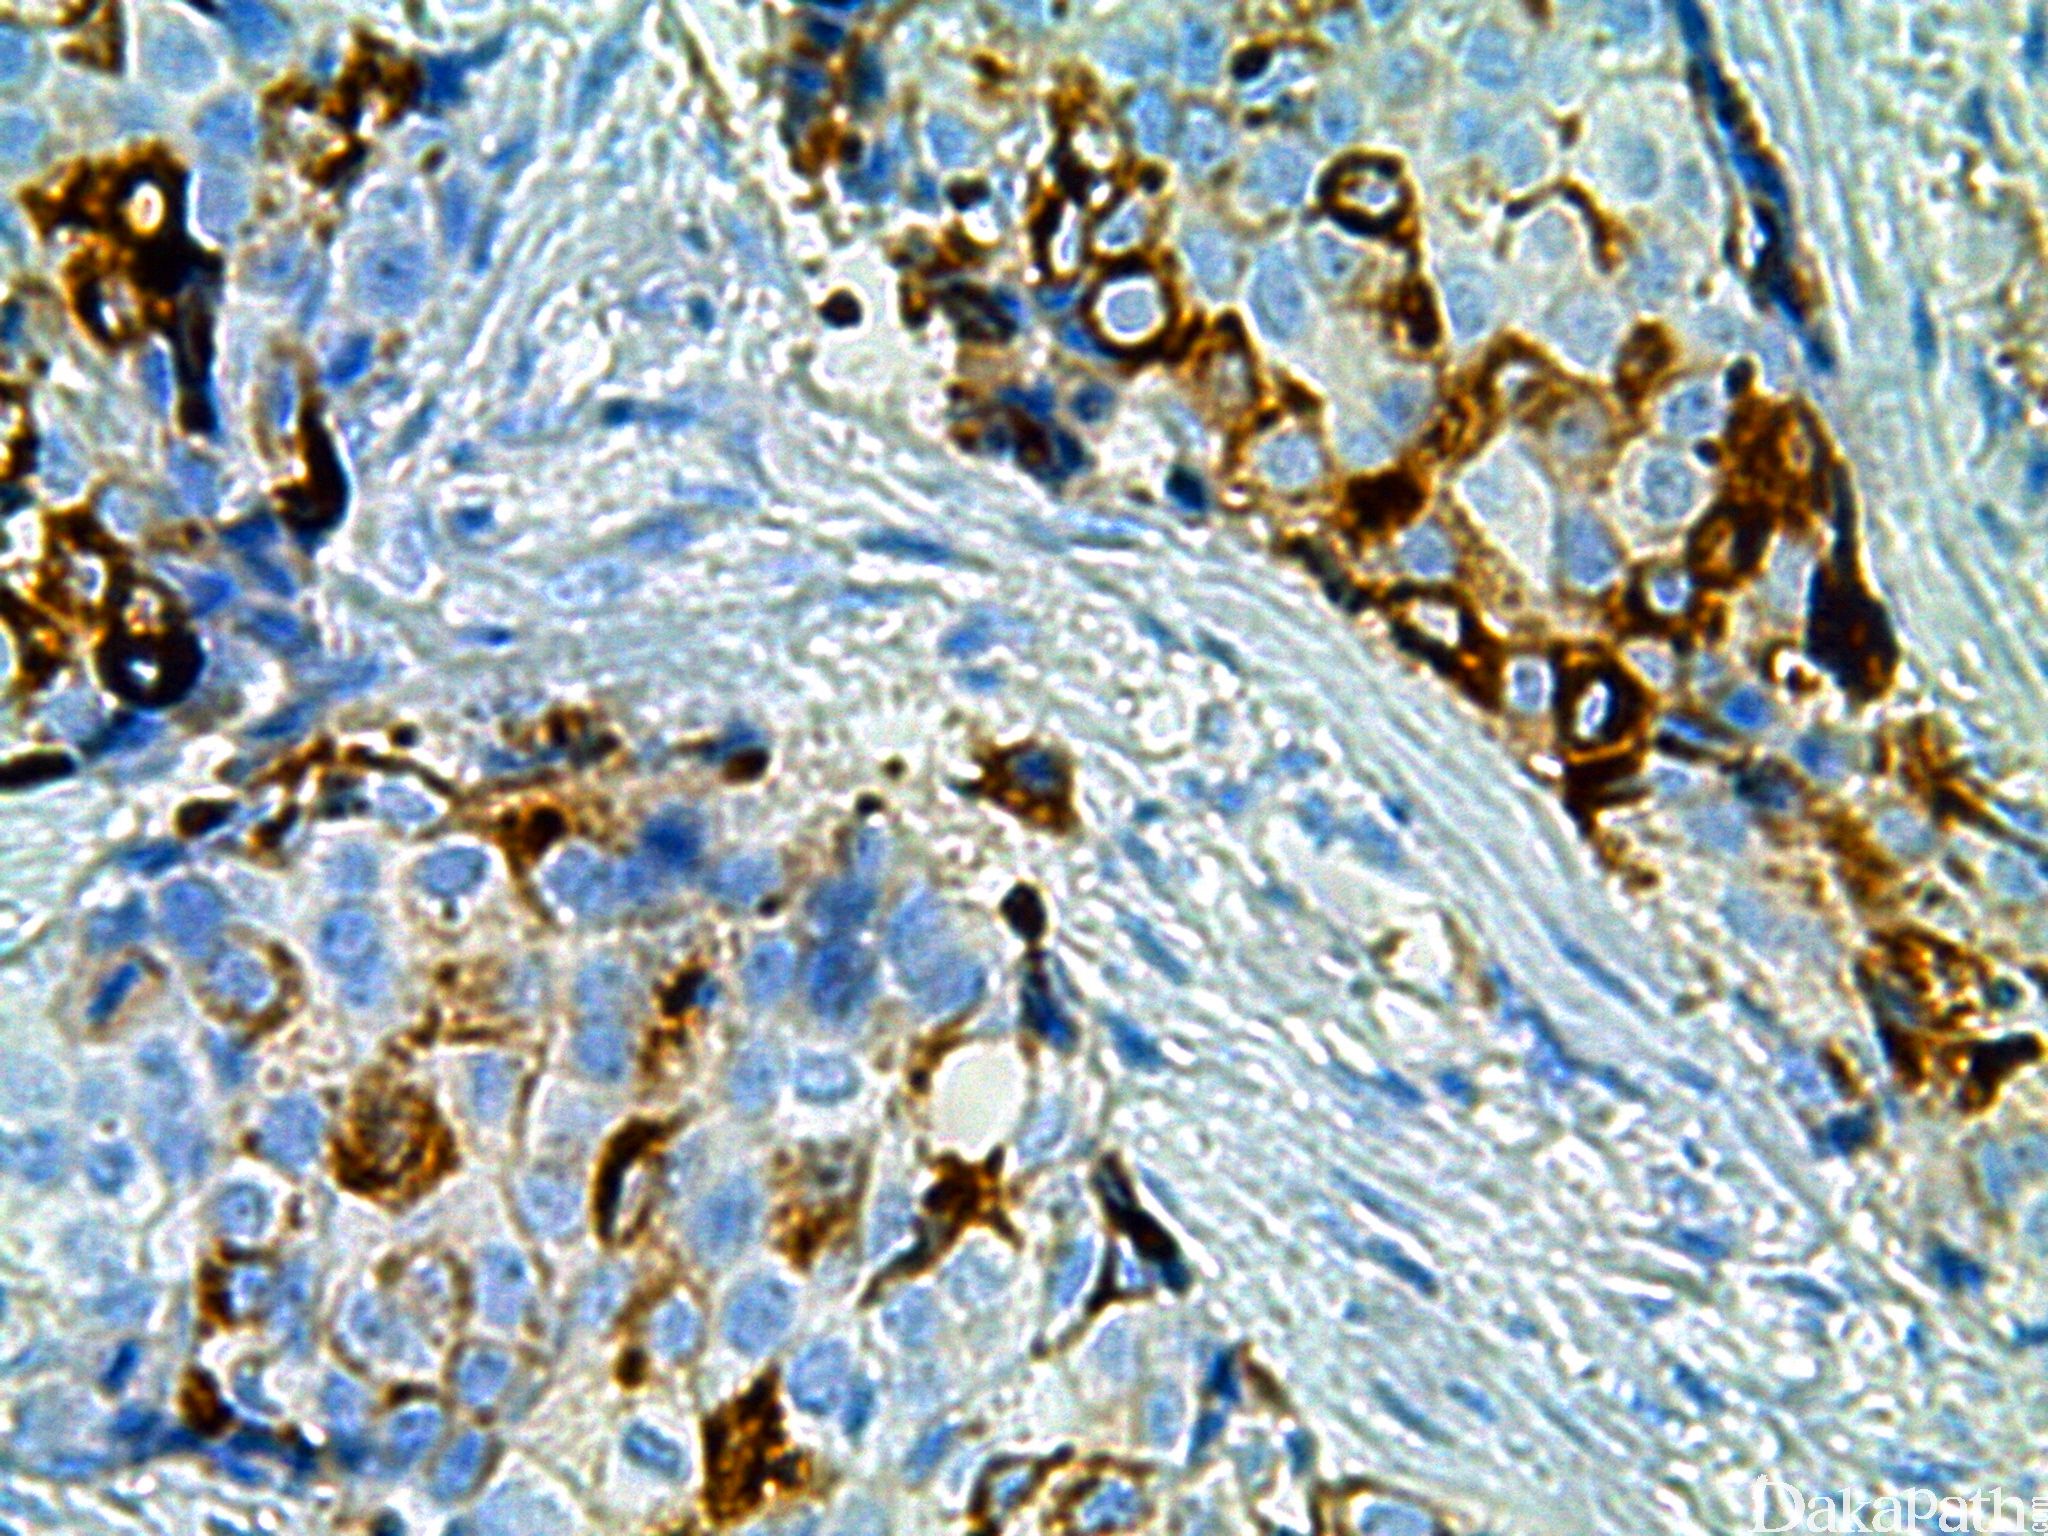

GCDFP-15

从乳腺囊泡病的囊泡液中提取的 15KDa 的蛋白,编码基因位于 7 号染色体,乳腺癌常产生该蛋白。正常乳腺仅小叶内及小导管单个细胞阳性。在顶浆分泌腺体、 泪腺、耵聍腺、Moll's 腺、下颌腺、支气管腺体、舌下腺和小唾液腺的胞浆中均有表达。

信号定位: 胞质